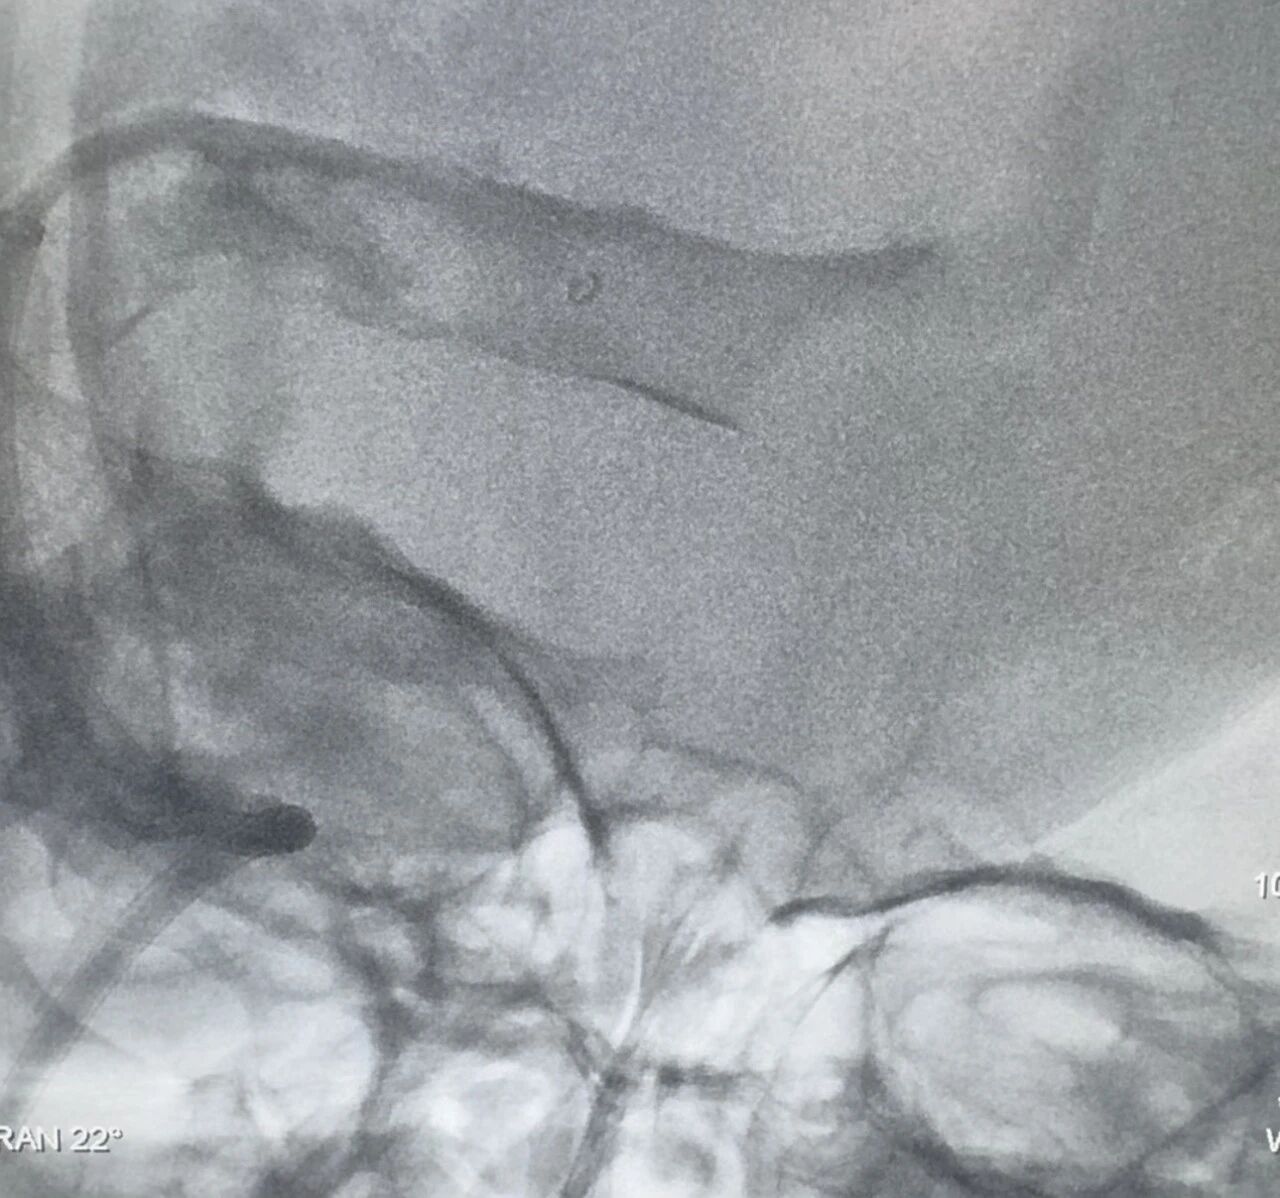

在与时间赛跑的抢救中,林镇洲与神经内科副主任阿地力江·阿布力米提主刀,迅速为阿女士实施经皮颅内静脉取栓术联合经皮颈静脉球囊扩张成形术。手术采取微创介入方式,通过颈静脉穿刺,将导管精准送达血栓阻塞部位,在影像引导下将血栓吸除、捕捉并清理干净,同时利用球囊撑开狭窄段,进一步改善静脉回流。这种方式无需开颅,创伤小、速度快,能够迅速降低颅内压力,是目前救治静脉窦血栓的关键手段之一。

得益于我院卒中团队的成熟经验和介入技术,手术过程顺利,成功取出多条暗红色血栓,使受阻的静脉通路重新畅通。术后患者被转入重症监护室进行严密监护,病情逐渐稳定并于 11 月 16 日转入普通病房。在近 20 天的精细化管理、抗凝治疗及康复护理下,患者头痛消失,言语、肢体活动恢复正常,无癫痫再发,出院时未遗留任何神经功能缺损。